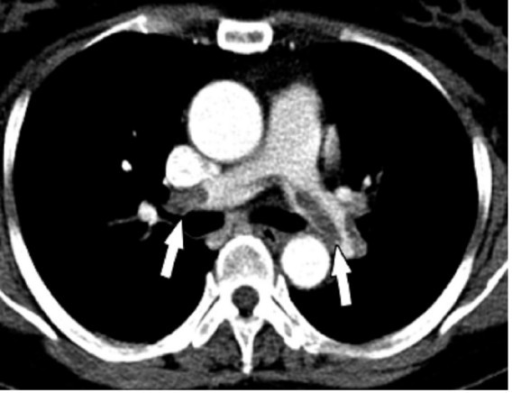

Pulmonary Embolism CT Scan

https://openi.nlm.nih.gov/detailedresult?img=PMC2020460_1476-7120-5-26-3&query=pulmonary%20embolism&it=xg&lic=by&req=4&npos=6